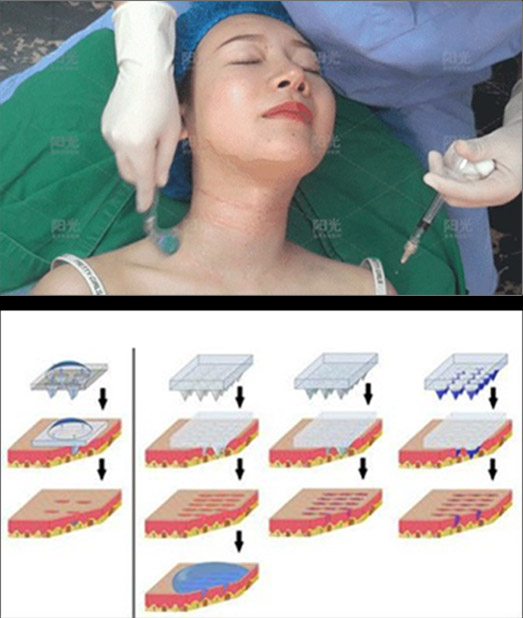

突破表皮屏障直达真皮层

Break through the skin barrier and reach the true layer

STEP 1 填充颈部缺失的组织容量

以透明质酸为母液(搭载多种氨基酸、L-肌肽和维生素等)注射至真皮层满足颈部肌肤的营养补给、填充组织容量缺失

STEP 2 修复断裂的纤维组织

将营养物质及活性成分精准、定量输送到颈部皮肤中胚层修复断裂纤维组织的同时刺激皮肤新陈代谢,促进胶原蛋白再生。

微→皮肤再愈合修复

刺激细胞代谢→新生细胞形成 同时改善微循环,提高颈部肌 肤通透性、弹性

生物活性物质→激活组织细胞, 组织加速加量修复和增生

实现肌体重建